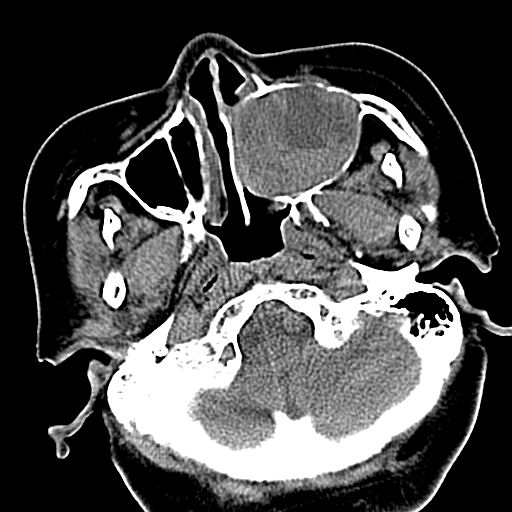

标题: CT19708:单侧上颌窦病变

老年患者,女。鼻塞多年。

考虑右侧上颌窦良性占位性病变,粘液囊肿可能性大;建议活检。

膨胀性生长,且骨质无破坏,说明时间久,良性;从密度,边缘看,内部还见坏死区,应该是实性肿瘤,定性,影像学无绝对的特异性

病灶密度很不均匀,骨壁膨胀中有断裂,考虑内翻乳头状瘤可能性大,粘液囊肿不排除

膨胀性生长,且骨质无破坏,说明时间久,良性;从密度,边缘看,内部还见坏死区,应该是实性肿瘤,定性,影像学无绝对的特异性,考虑内翻性乳头状瘤可能